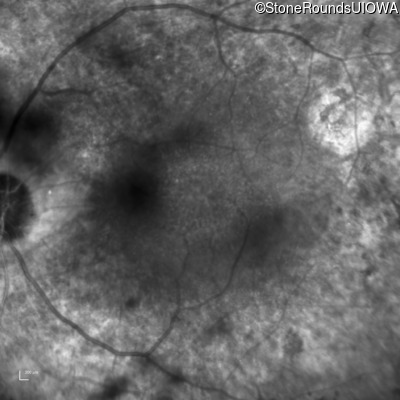

Infrared Fundus Photograph - Right - 20/32

Exemplar

Infrared Fundus Photograph - Left - 20/32